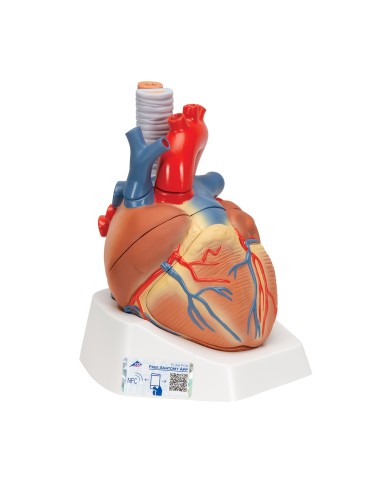

Modello di cuore di alta qualità scomponibile in 5 parti

Modello di cuore di alta qualità scomponibile in 5 parti

La parete anteriore del cuore è staccabile per poter vedere i ventricoli.

Realizzato in stampa 3D ad elevatissima risoluzione a colori.

Realizzato in stampa 3D ad elevatissima risoluzione a colori.

Realizzato in stampa 3D ad elevatissima risoluzione a colori.